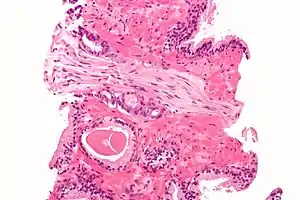

الخزعة

إذا اشتُبِه بوجود سرطان البروستات عند أحد المرضى، يتم أخذ خزعة على وجه السرعة. حيث يقوم أخصائي المسالك البولية أو أخصائي الأشعة بأخذ عينة من أنسجة البروستات عن طريق المستقيم، فيتم إدخال المنظار وتستعمل إبرة مجوفة لإزالة ما يقدر بثلاثة إلى ستة إنشات من كل جانبٍ في البروستات في أقل من ثانية، وعادة يتم القيام بها كإجراء روتيني في العيادات الخارجية، إذ لا يتطلب هذا دخولاً أو تنويماً في المستشفى. وقد أوردت التقارير أنَّ ما نسبته خمسة وخمسون في المئة من الرجال يشعرون بعدم الراحة أثناء إجرائها.[75]

مقياس (نقاط) جليسون